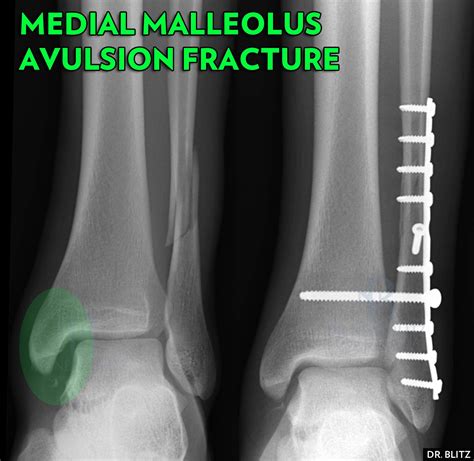

• X-Rays: The primary imaging tool for diagnosing fractures. X-rays can show the location and severity of the fracture.

• CT Scans: Provides detailed images of the bone structure, useful for complex fractures or when surgical planning is required.

For more severe fractures, surgery may be necessary to realign the bones and stabilize the joint. Surgical options include:

• Open Reduction and Internal Fixation (ORIF): Involves making an incision to realign the bones and using plates, screws, or rods to hold them in place.